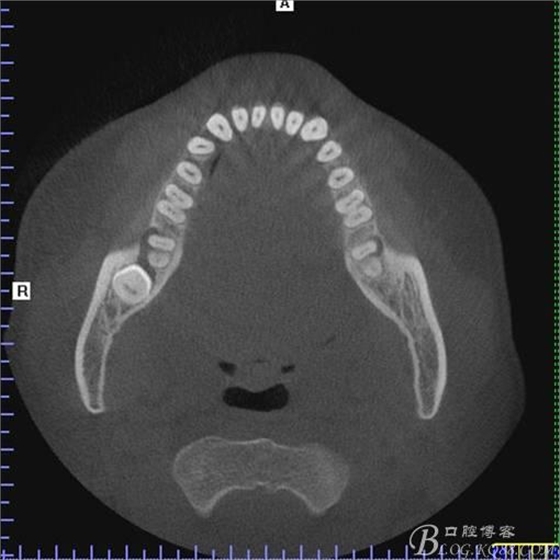

二、術(shù)前CBCT影像:

圖1.47牙冠的近中面緊鄰下頜神經(jīng)管

圖2.判斷47牙根是否吸收

圖3.通過(guò)矢狀面和冠狀面來(lái)判斷48與下頜管及47的關(guān)系

圖4.水平方向48與47之間的關(guān)系

圖5. 48的三維視圖

圖6.測(cè)量48頰、舌側(cè)骨板厚度。

圖7.測(cè)量牙冠近遠(yuǎn)中徑的大小及遠(yuǎn)中骨板的厚度